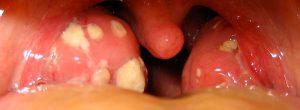

Piedras en las amígdalas: qué son y qué hacer con respecto a ellos